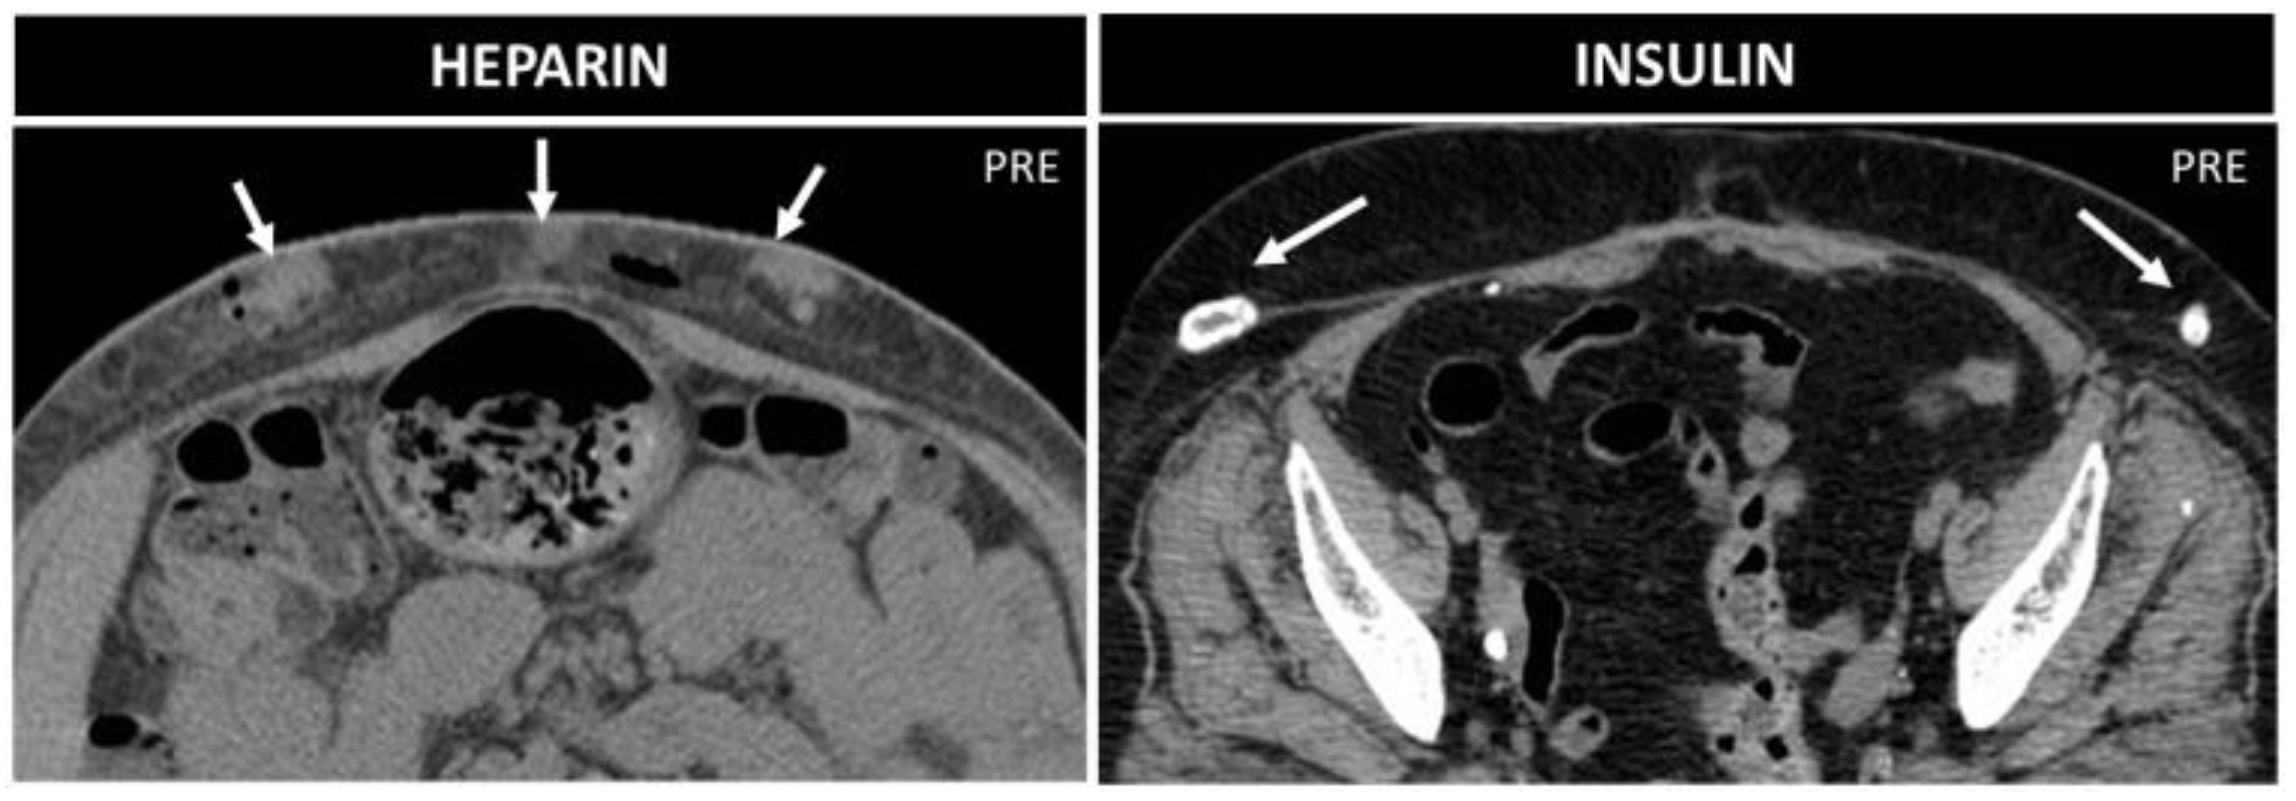

5.3. Subcutaneous Drugs